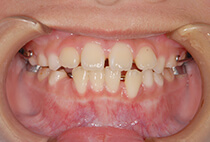

小学2年生の終わり、

「将来は外科矯正が必要」と言われた受け口の女の子。

小学生の成長力を最大限に生かすため、

上顎の成長促進・過蓋咬合の改善・機能訓練を同時にスタートしました。

1年後(小3 → 小4)

かみ合わせもお顔立ちも大きく改善。

その後も機能訓練×かみ合わせの維持をコツコツ継続。

急速拡大装置、上顎前方けん引装置、コルチコトミー

診断の結果は、以下が原因の骨格性反対咬合。

反対咬合でよくあるケースです。

治療方法は、小さな上顎の成長誘導。

急速拡大装置と前方けん引装置を使用します。

成長のピークに合わせて上顎をもう一度拡大し、前歯のかみ合わせをさらに安定化。

成長期の波に合わせることで、より調和の取れた横顔へ。

治療開始から6年後。

治療終了後2年経っても、安定したかみ合わせと自然な横顔をキープ。

2年生で外科矯正と言われた受け口も、4年生になる頃にはすでに「バランスの良いお顔立ち」に。のびのびと成長期を過ごすことができました。